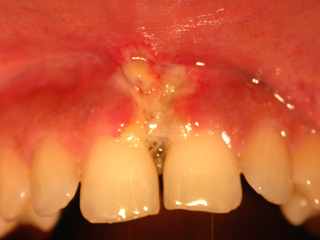

Dopo una settimana di trattamento

Dopo una settimana dall’intervento eseguito con elevata intensità di potenza, inizia una guarigione superficiale dei tessuti (quella bianca è la classica struttura di fibrina che si produce nelle ferite ampie e profonde da laser).

A un mese dall’intervento la guarigione è perfetta e la paziente soddisfatta dell’esito.